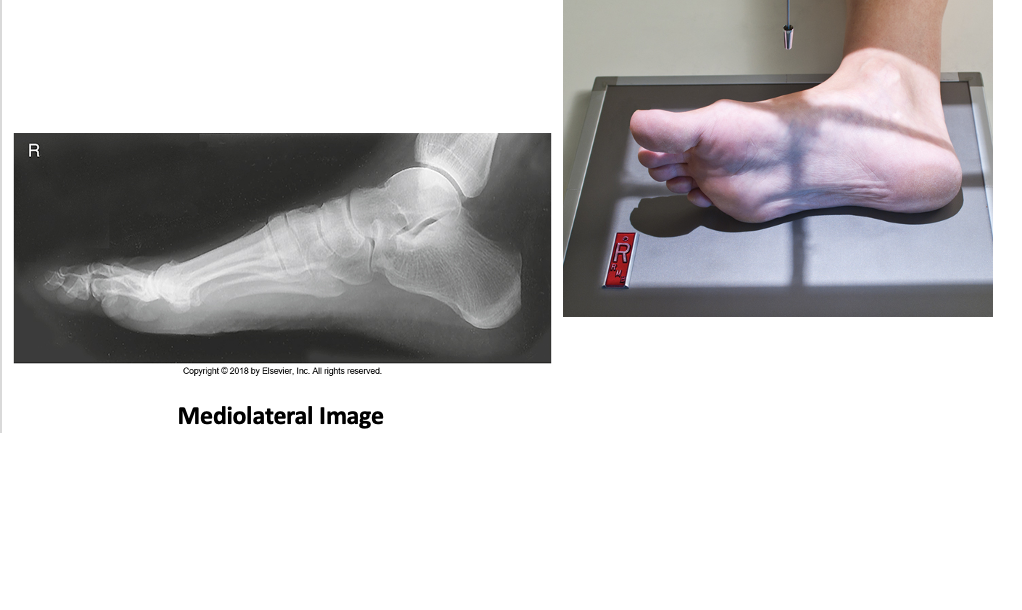

Lateral Foot

• IR 10x12 portrait (14x17 may be used if patient’s foot is large), 40 SID

• Place patient in lateral recumbent position. Flex knee of affected limb about 45º, place opposite leg behind affected leg to prevent over-rotation. Dorsiflex foot for a true lateral foot and ankle. Place leg and knee support so plantar surface is perpendicular to IR (do not over-rotate). Align long axis of foot to long axis of IR center base of MT’s to IR.

• CR perpendicular to medial cuneiform (at level of 3rd MT base). Collimate to skin margins & 1” proximal to ankle joint (approx. 1” all sides).